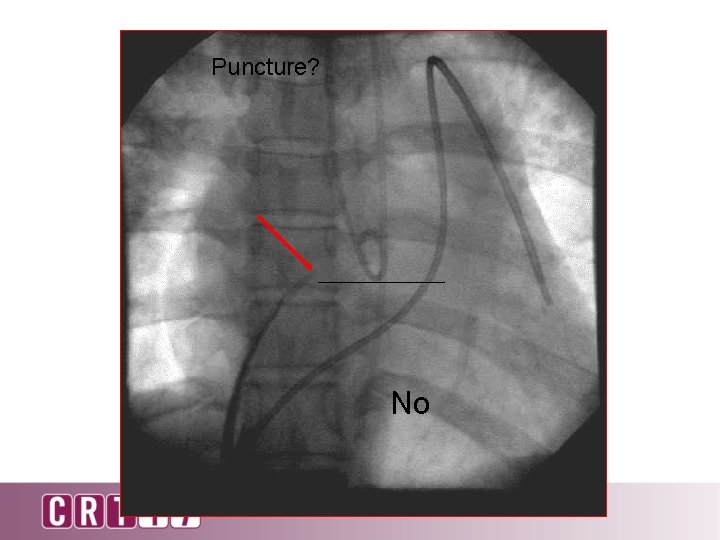

Puncture? No

Puncture? No